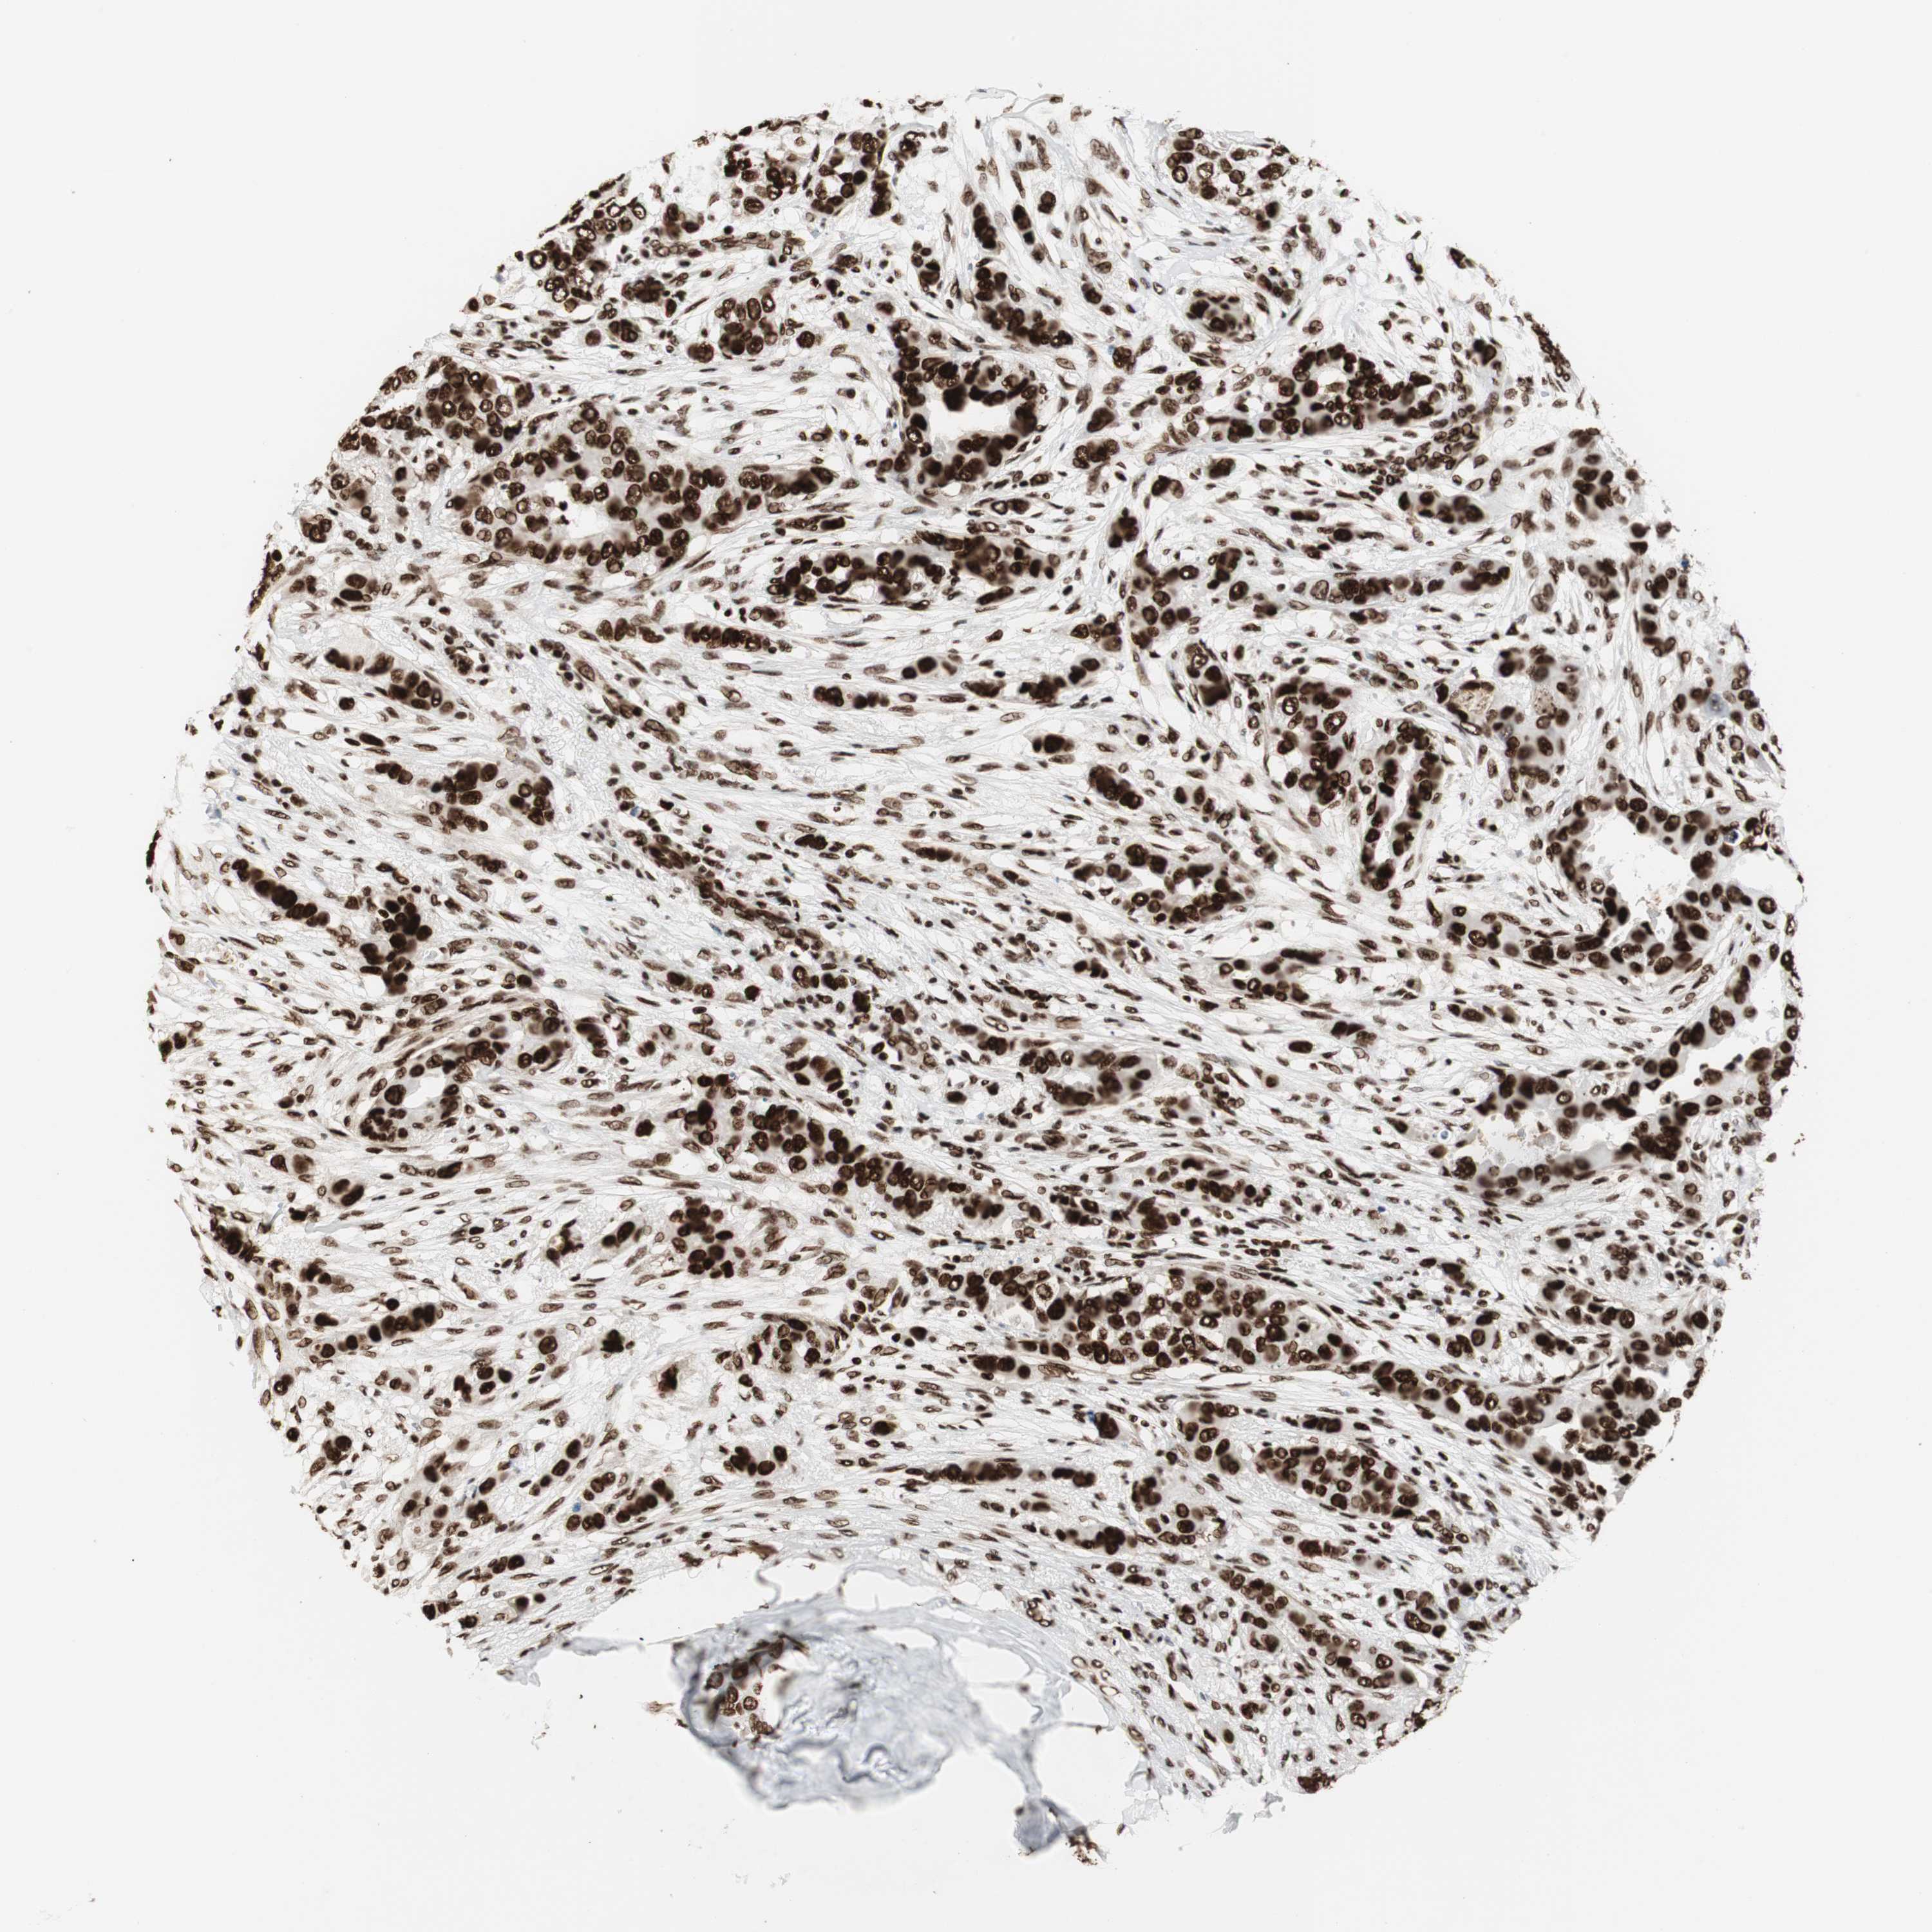

BRCA TCGA BRCA VALIDATION PROTEIN EXPRESSION